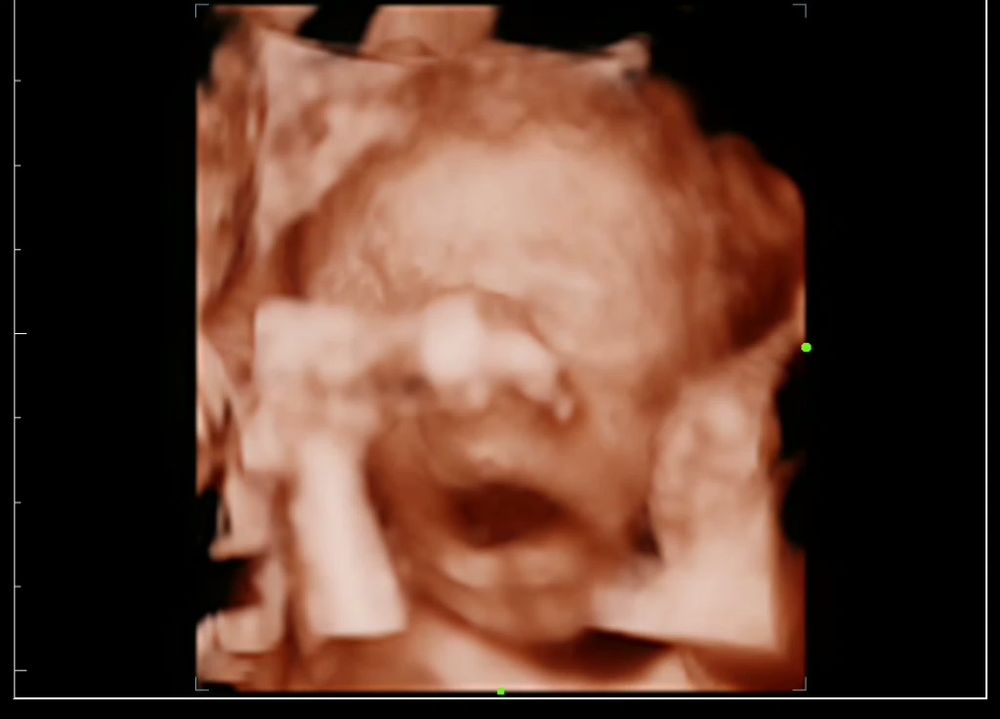

Сделала на 24 недели ровно. Было видно хорошо, но дочь спала все узи, целый час пытались растормошить и пятку на нос закинула 🤣 Изображение Это она зевушкала во всю 🤭 Изображение